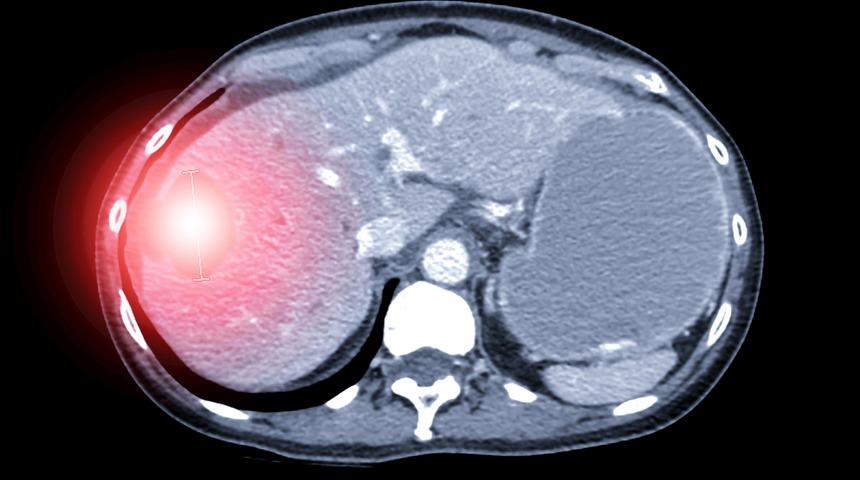

“Bu parazitin en yaygın taşıyıcısı köpekler olmakla birlikte kurt, tilki gibi tüm et yiyen hayvanlarda taşıyabilirler. Parazit köpeklerin bağırsaklarında yaşar. Köpek dışkısı ile atılan yumurtalar rüzgâr ve yağmur etkisi ile toprağa yayılır. Bu yumurtalar aylarca toprakta canlı kalır. Yumurtaların bulaştığı sebze, meyve ve yeşilliklerin iyi yıkanmadan yenmesiyle de insanlara bulaşır. Aynı şekilde hastalıklı köpeğe el ile temastan ya da parazit yumurtasının bulaştığı bir toprağa dokunduktan sonra el yıkanmadan yemek yenmesi de başka bir bulaşma yoludur. Tıpkı insanlar gibi koyun, keçi, sığır gibi otla beslenen hayvanlar da yumurtaları alarak hastalanırlar. Alınan bu yumurtalar bağırsak duvarını geçer, kan ve lenf yoluyla öncelik sırasıyla karaciğer, akciğer ve diğer organlara yerleşerek kist formunda yaşamlarını sürdürürler. Kist en çok karaciğerde, ikinci sıklıkta ise akciğerde yerleşir. Nadiren de dalak, böbrek, kalp, beyin, göz yuvasında bile hastalığa yol açabilir.”

Prof. Dr. Yaprak, kistin karaciğerde oluşması sırasında başlangıçta hiçbir belirtinin gözlemlenmediğine işaret ederek, “Ancak yıllar içinde kistin büyümesi ile bir dolgunluk hissi ve ağrı, bulantı, kusma gibi şikayetler olur. Kist safra yollarına bası yaparsa ya da açılırsa sarılığa yol açar. Kist patlarsa ölümcül bir alerjik reaksiyon gelişebilir. Bazen de tesadüfen çekilen ultrasonografi veya tomografilerde varlığı fark edilir. Kist hidatik tedavisi kistin yerleştiği organa, organdaki yerine, çapına aynı zamanda da evresine göre değişmekle birlikte tedavi seçenekleri arasında bulunan ilaç tedavisi, PAIR dediğimiz kistin dışarıdan konulan bir kateter ile boşaltılması ve ameliyat yöntemlerinden en etkili olanı ameliyatla kistin tamamen alınmasıdır” değerlendirmesinde bulundu.

Karaciğerde ekinokok parazitinin yol açtığı başka bir kist tipi olan alveolar hidatik hastalığında ise tedavinin farklı olduğuna dikkati çeken Prof. Dr. Yaprak “Alveolar tipte olan ekinokok paraziti yine köpeklerin dışkısıyla toprağa karıştığı gibi tilki, çakal, kurt gibi hayvanlarda paraziti yayabilirler. Alveolar hidatik hastalığında kist adeta bir tümör gibi karaciğer içinde yayılır ve bazı hastalarda karaciğerin tümünü değiştirmek yani karaciğer nakli gerekebilir” dedi.